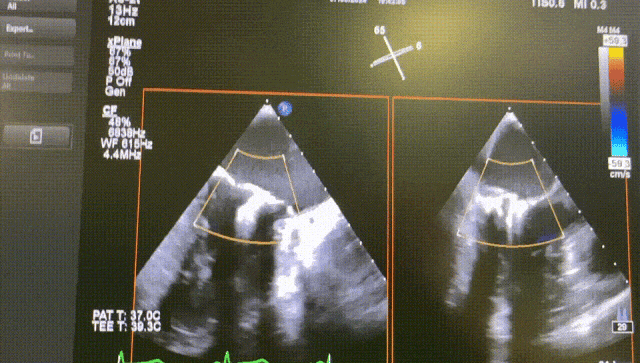

Case 2

The patient was a 73-year-old male with mitral valve p2 prolapse, severe calcification of the posterior leaflet root, severe mitral regurgitation with an orifice area of 4.1 cm². After evalsuation, transcatheter mitral edge-to-edge repair (TEER) was performed using the DragonFly™ system on the patient.

The procedure was smooth and uneventful. A SW0609 mitral clip was implanted to close the leaflet at P2, and the patient's regurgitation disappeared, with a mitral pressure difference of 2 mmHg and a significant decrease in left atrial pressure.

Before

After